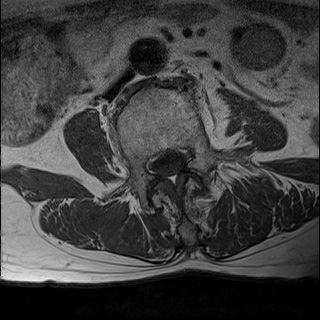

Ӵϲ ɿ ô ô 㸮 ٸ ̾ϴ. ϵ Ͻð ܻ 㸮 20⵿ ͽϴ. mri ˻ ɿ Ȳ ʹ ؼ Ȳ̶ ߽ϴ. ϻȰ ϰ 鼭 ½ϴ. ̴ ø鼭 Ͻô Ȳ ̷ ġ ص ȸ ϴ. δ Ҵµ, ù ȸԲ ˷ֽ ϰ β ϰ, ˷ֽ ü ƮĪ ϸ鼭 ȭǸ鼭 Ӵϲ ȸų ְ ǰ, β 鼭 ʴ β ؾϴ ŷο 1ϸ ijħ ڸ ǥ Ʈ ߽ϴ. ȸ ȭϽø鼭 Ϸ簡 ٸ ȸǽð 4ְ Ǿ Ǯ鼭 ¦ ҽϴ. ħ ȸ ȭϸ鼭 ڼ ü ƮĪ ϴ. ȥڼ Ͻʴϴ. ٳø鼭 ó Ͻ ʴϴ. ̾ ְ ̳ ߵ ʰ ϴ ȸԲ Ͻʴϴ. ʹ ϸ鼭 ϴ. Ȩ - ϱ ٴ Ȳ MRIԴϴ. |